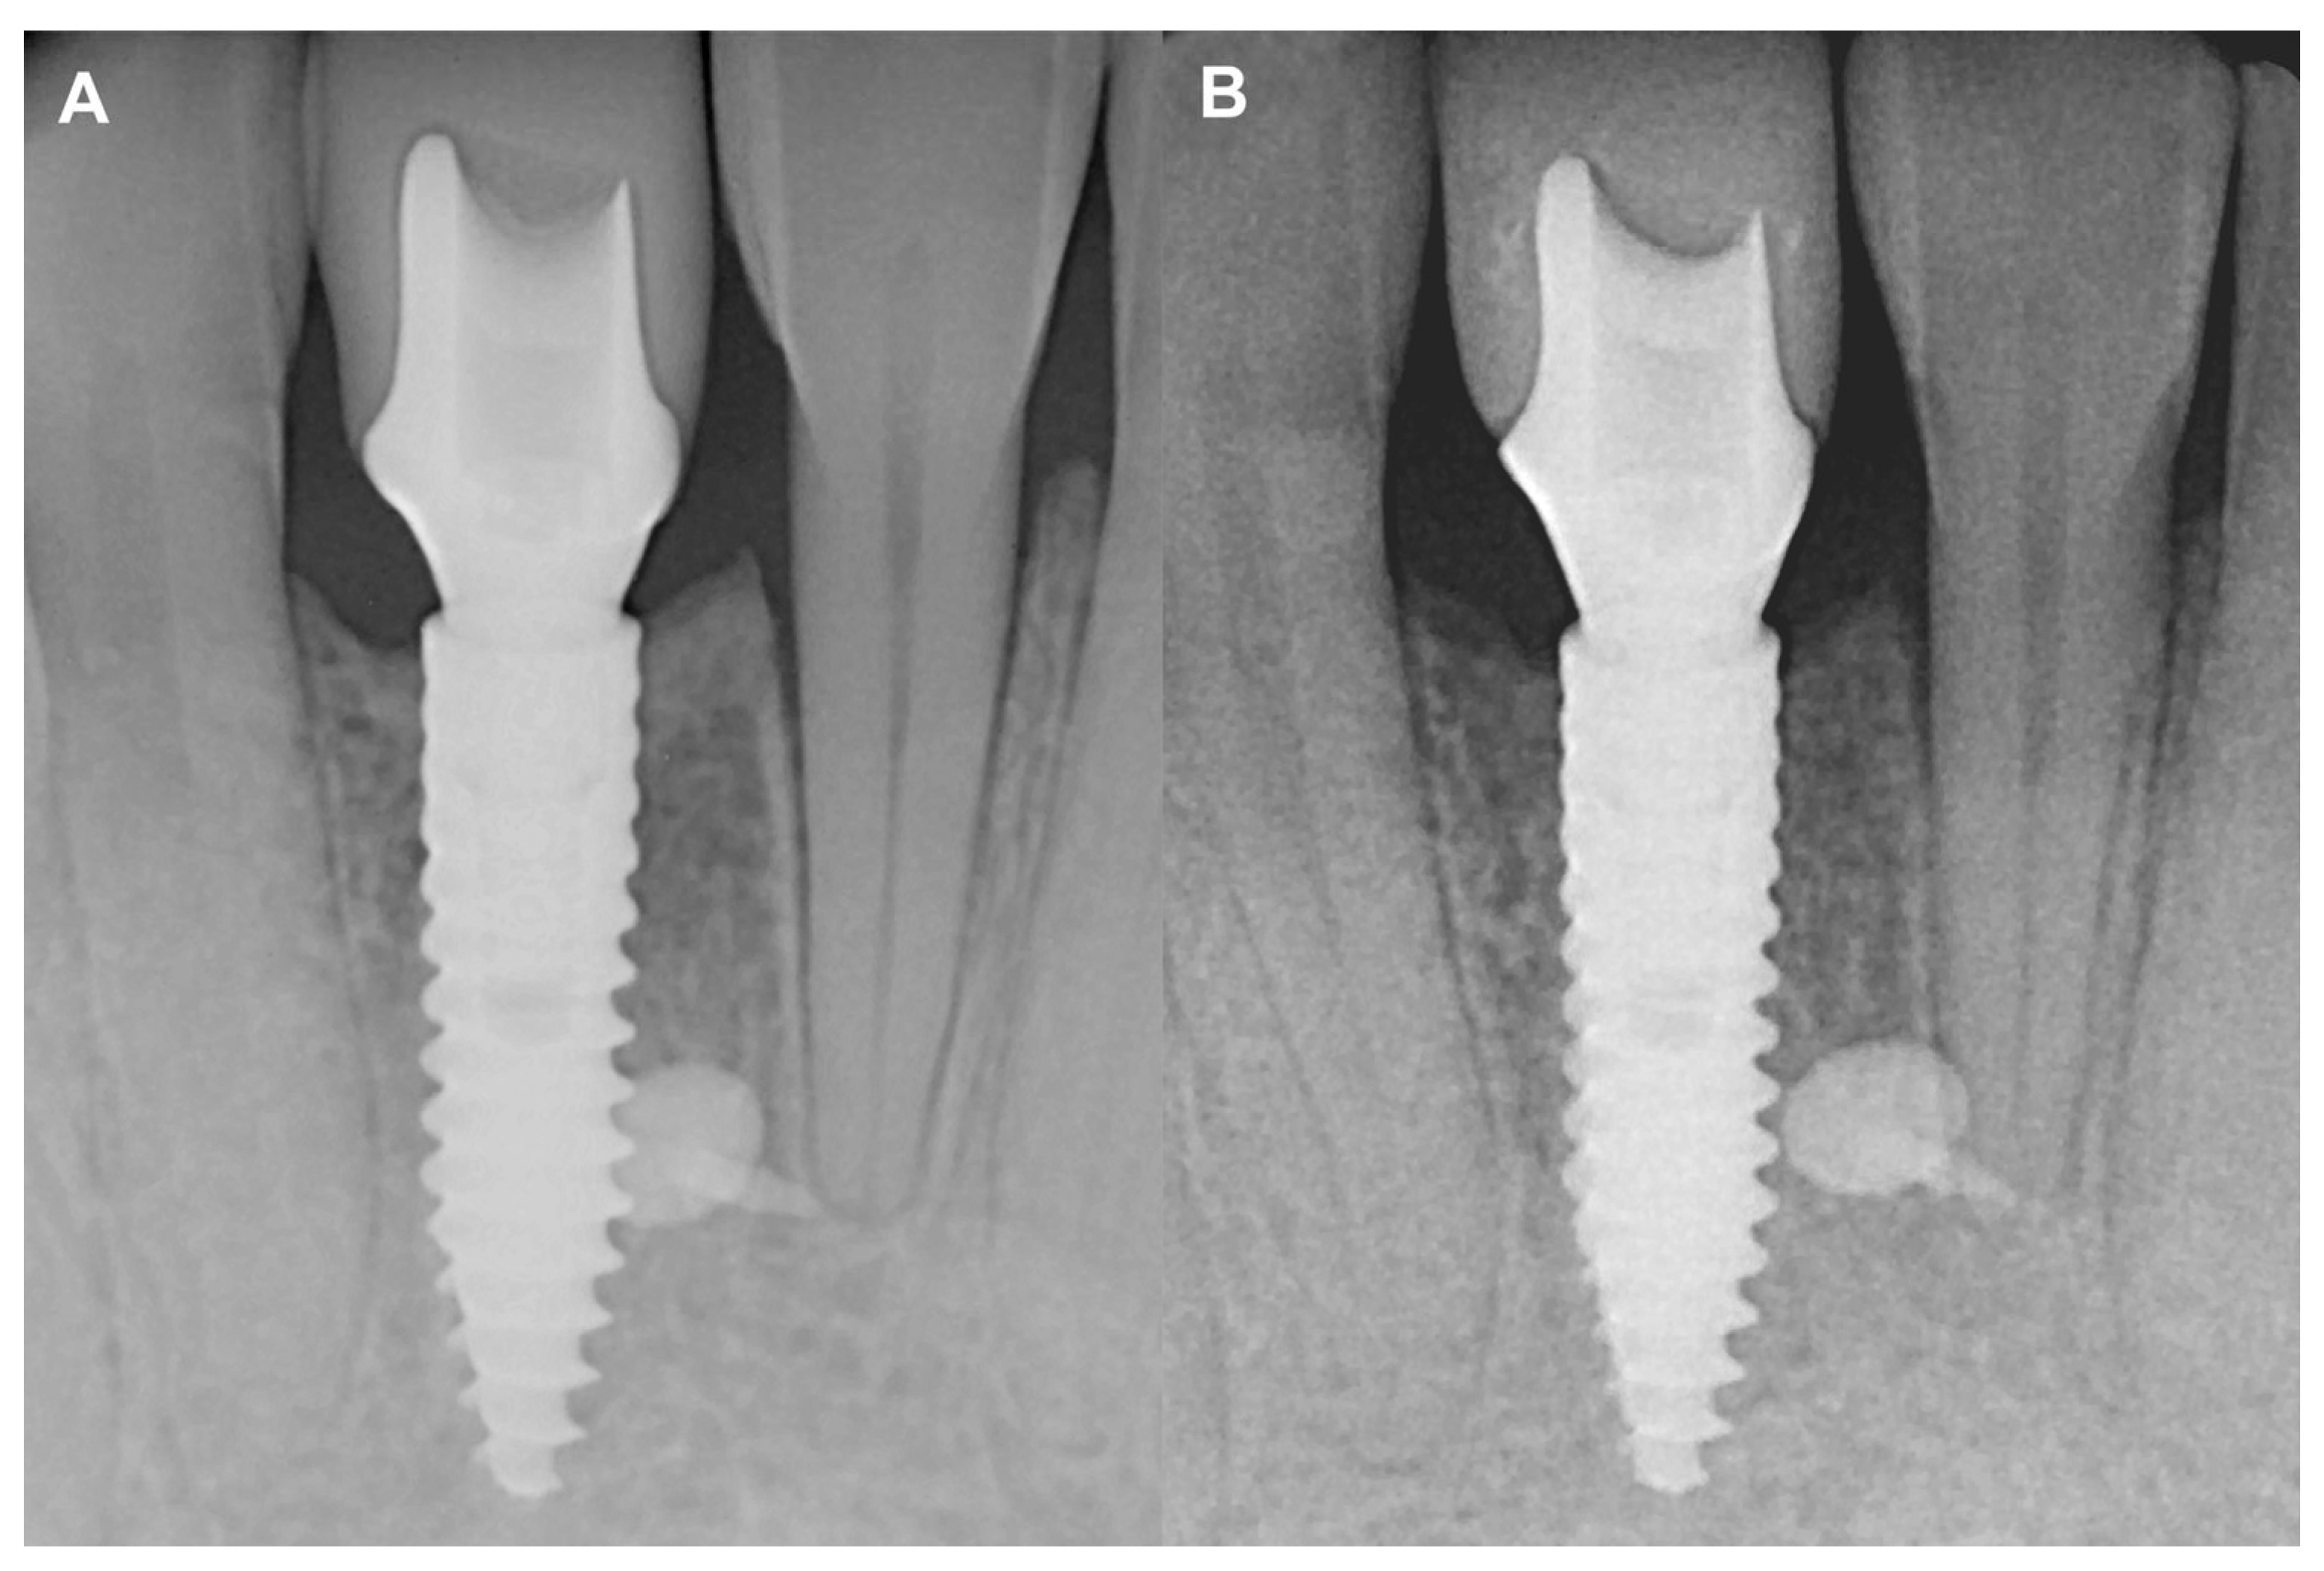

Figure 5.

Two-year follow-up of Case #1. (A): Intraoral radiograph at the delivery of the final restoration; (B): Intraoral radiograph at two-year follow-up.

Figure 7.

Two-year follow-up of Case #2. (A): Intraoral radiograph at the delivery of the final restoration; (B): Intraoral radiograph at two-year follow-up.

No marginal bone loss was detected in the long term when comparing the IR after the delivery of the final restoration to the IR of the two-year control, although increased corticalization and slight coronal hard tissue creeping were detected (Figure 5). The data are summarized in Table S1.

At the two-year follow-up, the marginal bone was stable, and no resorption was visible (Figure 7). The data are summarized in Table S2.

The current study has reported two-year follow-ups using the resorbable magnesium barrier membrane. The IRs acquired after the delivery of the final prosthetic restoration were compared to those at the two-year follow-up and stable marginal bone contours were observed. In both cases, a stable peri-implant hard and soft tissue environment was established, and neither of the inserted implants showed marginal bone resorption or peri-implant inflammatory processes.